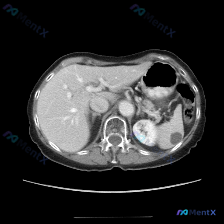

这张是腹部CT软组织窗的横断面:

- 肝脏、胰腺、肾上腺、肾脏:这张切面里看到的部分都还好,肝实质均匀,肝缘光滑,肾皮质髓质分界也清,肾上腺区没见明显肿大。

- 脾脏:重点来了,脾脏里能看到一个类圆形的低密度灶。

- 密度:很均匀,接近水样或者略高一点

- 边界:相对清晰、锐利

- 周围:脾实质看起来没被浸润,也没明显压迫周围血管

- 腹腔环境:没见腹水,脂肪间隙挺清楚的,没有明显渗出或条索影;腹膜后淋巴结也没见肿大;大血管管壁看起来也还好。